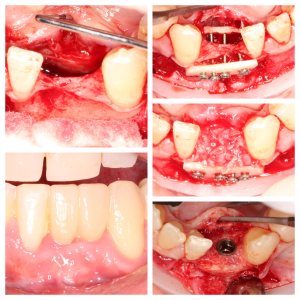

• During the first stage of surgery, your dentist or specialist will put a dental implant into your jawbone beneath the gum tissue. The gum tissue is then stitched back into place. As the tissue heals, the implant will bond with the bone and attach to the gum. It can take several months to heal.

• During the second stage of surgery and once the tissue is healed, your dentist or specialist will attach an abutment to the implant. An abutment is a post that connects the replacement tooth to the implant. In some cases, the first and second stage of implant surgery may be done in one single stage.

Surgical advances with SAME-DAY IMPLANTS in Vancouver BC

Using the most recent advances in dental implant technology, Dr. Noroozi is able to place single stage implants. These implants do not require a second procedure to uncover them but may require a minimum of six weeks of healing time before artificial teeth are placed. There are even situations where the implant can be placed at the same time as the tooth extraction and the artificial tooth can be inserted immediately following the implant placement – further minimizing your number of surgical procedures.

General Disclaimer: The results in the photographs are examples only and do not imply any certainty of the result of a procedure, and all outcomes are subject to the circumstances of the individual patient.